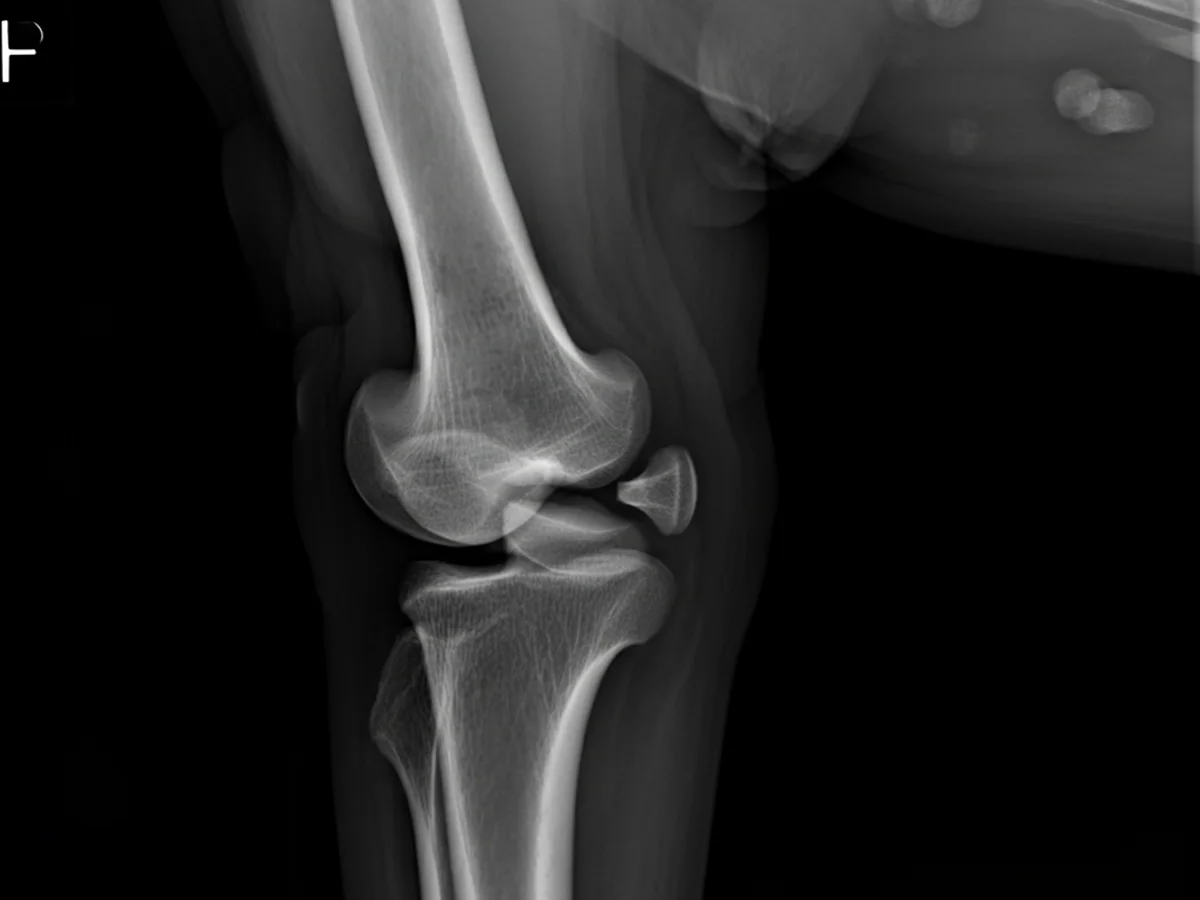

Zur Diagnose von Arthrose wird der Tierarzt zunächst eine gründliche körperliche Untersuchung Ihres Hundes durchführen, um den Bewegungsumfang und eventuelle Schmerzreaktionen zu beurteilen. Oft sind Röntgenaufnahmen erforderlich, um den Zustand der Gelenke genauer zu untersuchen. In einigen Fällen kann auch eine Ultraschalluntersuchung oder MRT notwendig sein. Diese Tests helfen, andere mögliche Ursachen für die Symptome auszuschließen und die Schwere der Arthrose zu bestimmen.